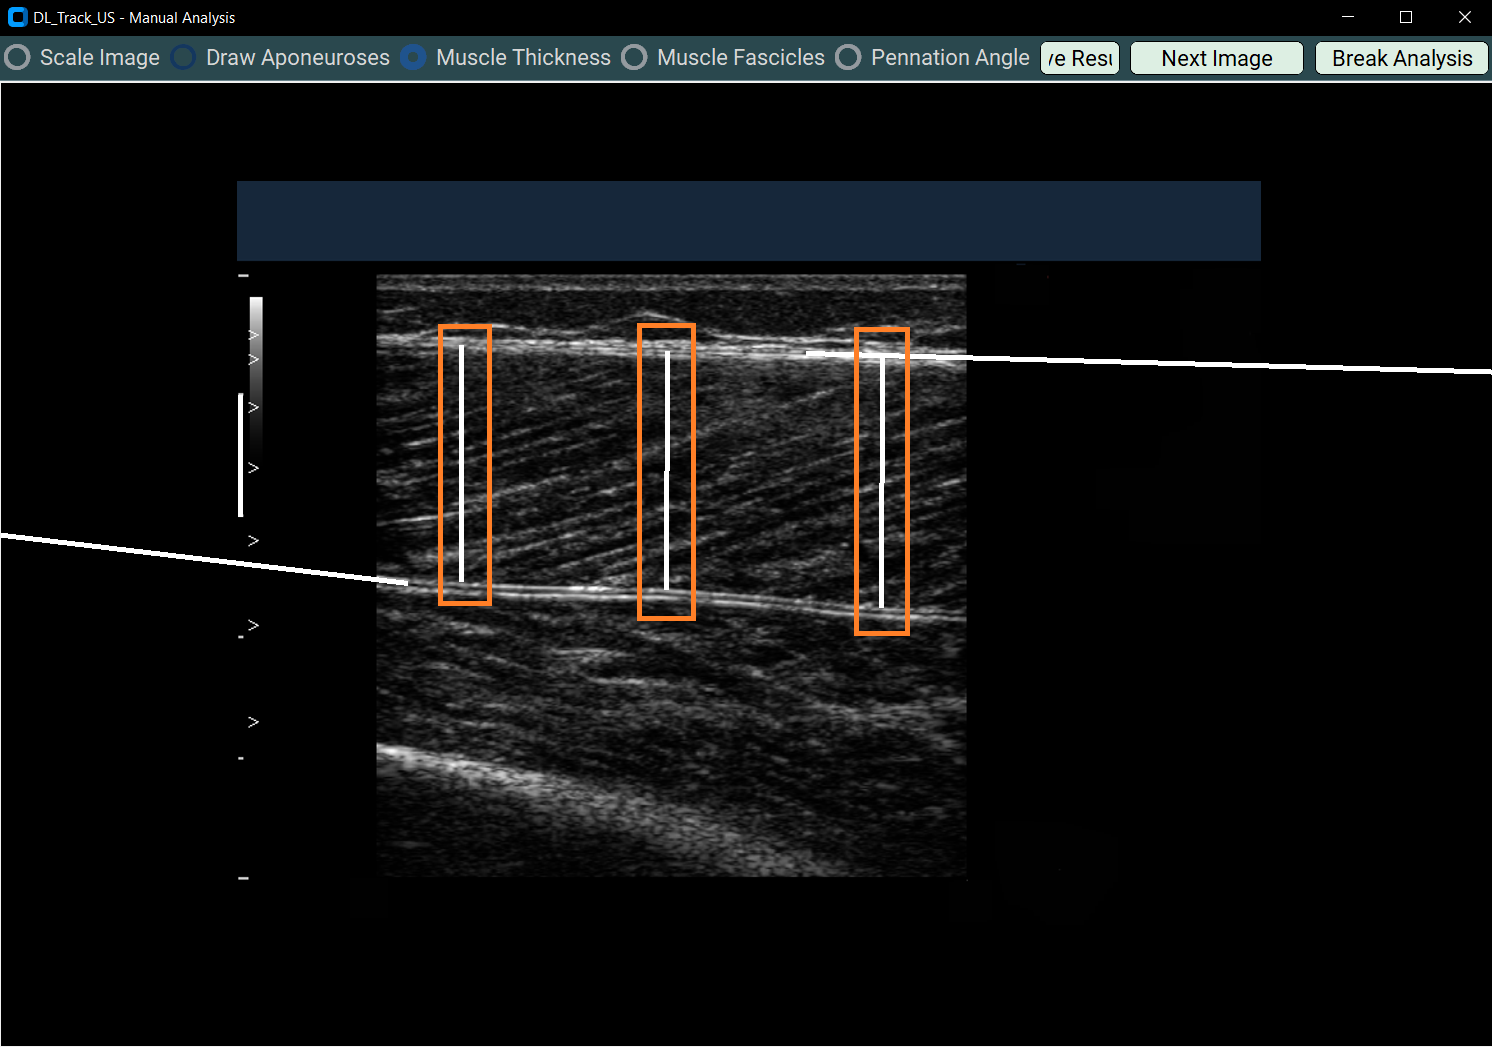

4.3 Measuring Muscle Thickness¶

- Select Muscle Thickness.

- Draw three straight lines from superficial to deep aponeurosis across the muscle image.